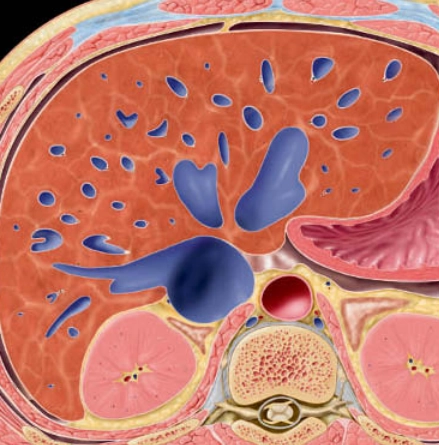

• Giải phẫu phân thùy gan theo Couinaud (Couinaud classification of hepatic segments)

• Thay đổi đậm độ gan thoáng qua trên CT (Transient hepatic attenuation differences - THADs)

• Tăng áp lực tĩnh mạch cửa (Portal Hypertension)